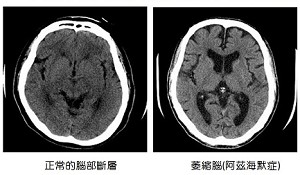

搶救失智大作戰---阿茲海默症之治療建議

阿茲海默症是老年人失智症最常見的病因(圖一),初期症狀是以短期記憶力受損為主。隨著疾病的進展,還包含其他漸進性且不可逆的認知功能障礙,例如記憶力退化、語言功能退化、操作能力變差、判斷力喪失、注意力不集中、定向力缺失等。行為的改變,例如淡漠、煩躁不安、精神症狀、社交能力受損等也都是臨床常見的表徵。